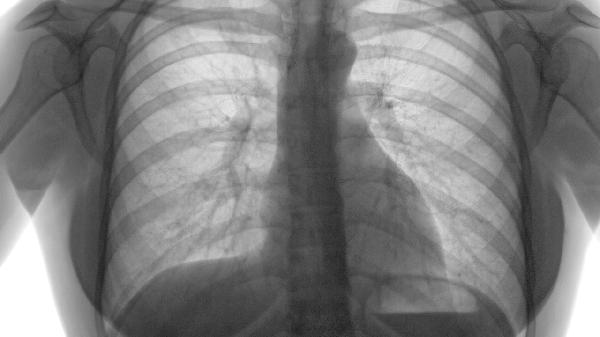

对于直径小于5毫米的肺部结节,通常建议定期随访观察。通过胸部CT检查监测结节变化,随访间隔一般为3-6个月。若结节在随访期间无明显变化,可延长随访间隔至1年。随访观察期间应戒烟,避免接触二手烟和空气污染物。

对于直径5-10毫米的可疑恶性结节,可考虑胸腔镜下肺楔形切除术。该手术创伤小,恢复快,术后住院时间短。术后病理检查可明确结节性质。微创手术适用于外周型肺结节,术后可能出现气胸、出血等并发症,需密切观察。

直径超过10毫米或高度怀疑恶性的肺部结节,可能需开胸肺叶切除术。该手术视野清晰,可彻底切除病灶及周围淋巴结。但创伤较大,术后恢复时间较长。开胸手术适用于中央型肺结节或多发结节,术后需进行呼吸功能锻炼。